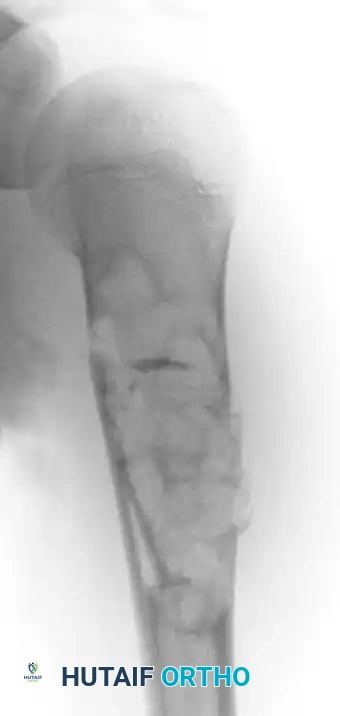

Fig. 20-22: (A and B) Pathological fracture of the right proximal tibia occurring through a large, expansile “brown tumor” of hyperparathyroidism in a 55-year-old woman.

Primary treatment is medical or surgical management of the underlying endocrinopathy (e.g., parathyroidectomy) by an endocrinologist or general surgeon. Following normalization of PTH levels, brown tumors typically remineralize and regress spontaneously. Orthopedic intervention is strictly limited to the stabilization of actual or impending pathological fractures. If a fracture occurs, intramedullary nailing or rigid plate osteosynthesis is required, as the structural integrity of the bone is severely compromised.

Early skeletal manifestations are typically limited to diffuse osteopenia and subperiosteal bone resorption (classically seen on the radial aspect of the middle phalanges). However, in advanced or neglected cases, the localized accumulation of osteoclasts and fibrous tissue produces a focal, expansile, lytic lesion known as a "brown tumor" (osteitis fibrosa cystica). The brown color is derived from extensive hemorrhage and hemosiderin deposition.

Histologically, a brown tumor is nearly indistinguishable from a true Giant Cell Tumor (GCT) of bone. However, subtle microscopic features favor hyperparathyroidism: